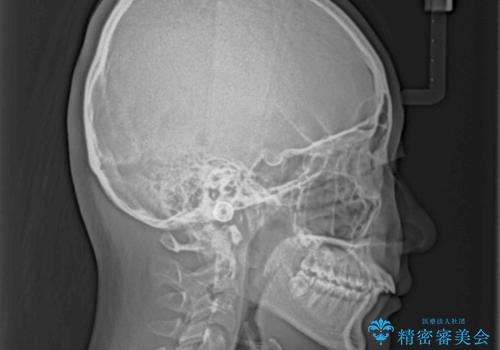

- 下顎前歯欠損による隙間と、上顎前歯の突出感を気にして来院された患者様です。

横顔に出っ歯の印象はありませんでしたが、下顎のスペースと上下前歯の前後位置の大きなズレを改善するために、上顎左右の第一小臼歯2本を抜歯しすることとしました。

口元が引っ込みすぎないようにするために、上下ともに臼歯を前方に移動させる必要があり、インビザラインでは対応できないため、表側のワイヤー装置にて矯正治療を行うこととしました。